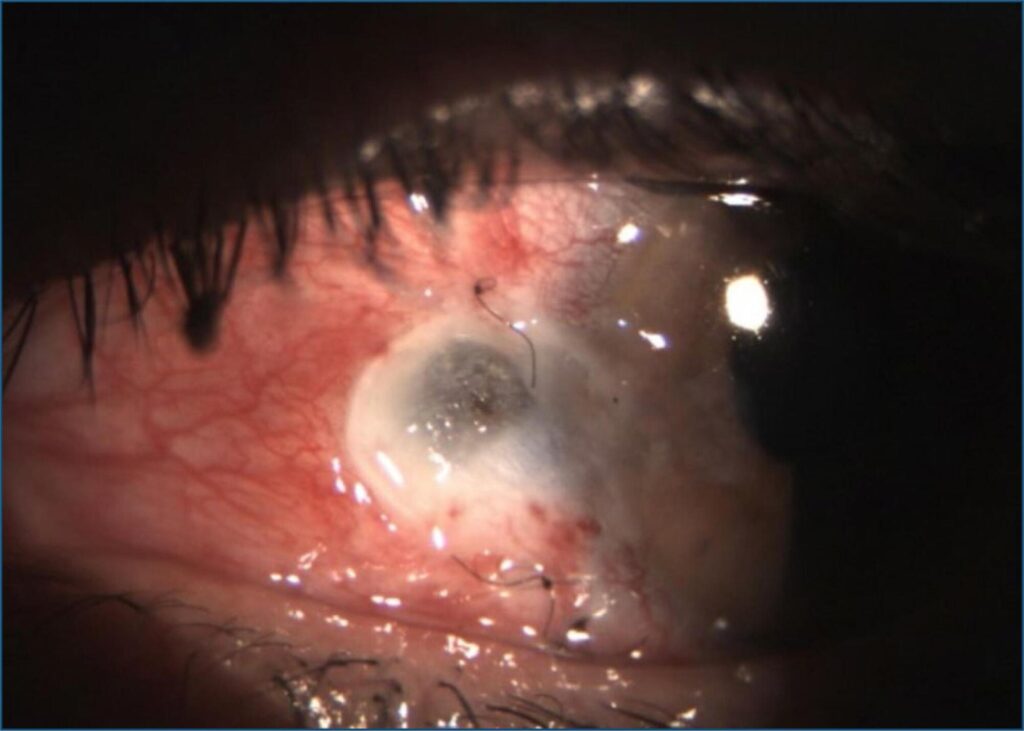

Retalho tarsoconjuntival em necrose escleral: relato de três casos

O objetivo deste estudo foi relatar uma série de três casos (quatro olhos) de necrose escleral pós-exérese de pterígio, em que se utilizou como tratamento a técnica de retalho tarsoconjuntival. Foram selecionados três pacientes que evoluíram para necrose escleral após tratamento cirúrgico de exérese de pterígio: o primeiro caso após técnica de esclera nua, com evolução para afinamento escleral no pós-operatório imediato; o segundo e o terceiro fizeram uso de betaterapia e apresentaram necrose escleral tardiamente. A técnica de recobrimento tarsoconjuntival foi executada pelo mesmo cirurgião. A recuperação foi satisfatória em todos os casos, do ponto de vista anatômico e funcional, sendo eficiente e segura. Apesar das escassas menções na literatura, essa técnica pode ser considerada uma boa alternativa para tratamento da necrose escleral.